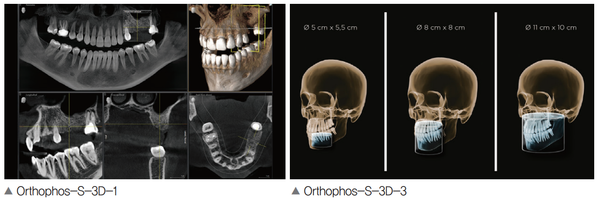

Orthophos 제품군은 선명한 이미지 품질이 장점이다. Orthophos S는 듀얼 센서 적용으로 선명한 이미지 품질과 높은 내구성을 제공한다. 또한 Ceph arm을 장착해 치아 교정에서도 정확한 진단이 가능하다.

3D 볼륨 촬영은 Ø 5cm × 5.5 cm부터 Ø11 cm × 10 cm까지 선택할 수 있으며 HD모드와 SD모드를 선택해 영상 품질 또한 선택이 가능하다. Orthophos는 한 번 회전하는 동안 최대 800개의 개별 이미지를 생성하는데 최대 80μm에서 고해상도 저노이즈 3D 볼륨영상을 제공한다. 이는 2D 파노라마를 촬영하는 수준의 선량이다.